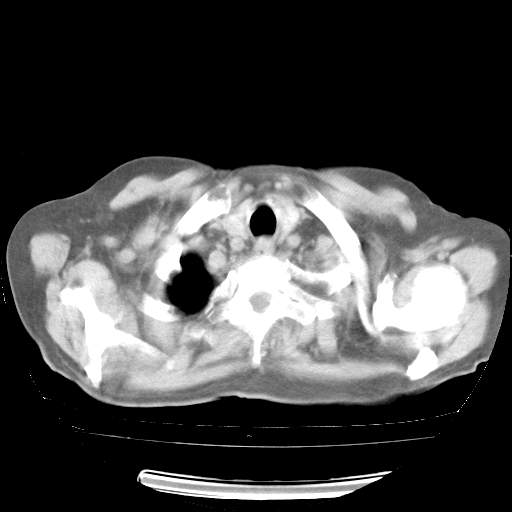

今天部分检查

轻微咳嗽,无痰,(体温正常时)R20次/分,P75次/分,双肺底、腋下可闻及少量捻发音。下肢轻度浮肿。